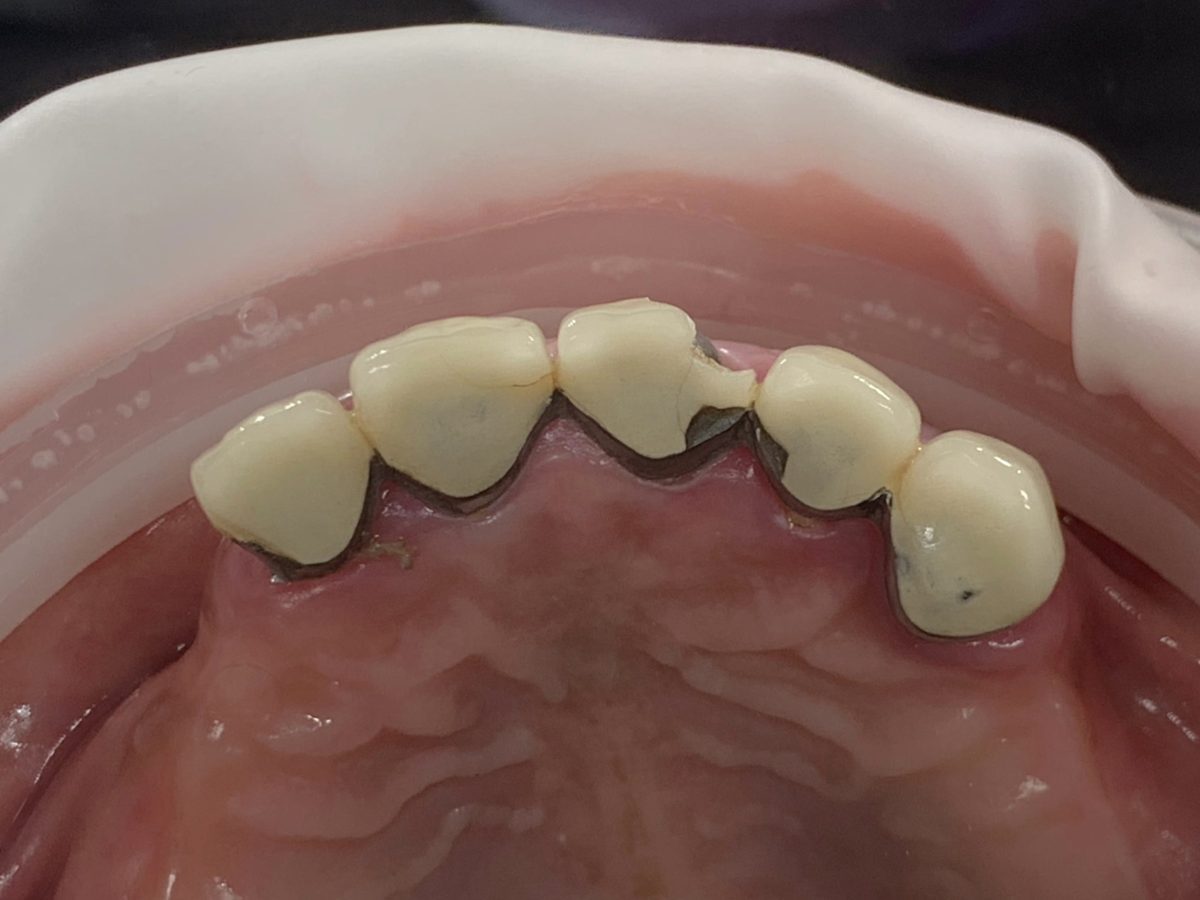

Full mouth rehabilitation is a comprehensive dental treatment designed to restore both function and aesthetics for patients with severely worn, damaged, missing, or failing teeth.

Treatment may include a combination of:

* crowns

* veneers

* dental implants

* bridges

* gum treatment

* bite rehabilitation

Each treatment plan is customized based on the patient’s oral condition and long-term goals.